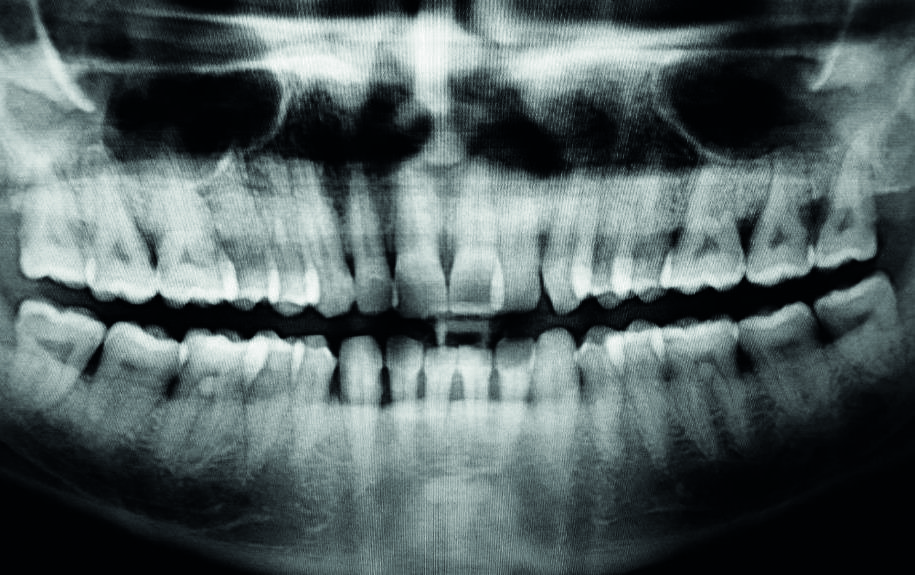

Fig. 2

Fig. 2 L’OPT mostra l’entità delle tasche parodontali e del riassorbimento osseo.